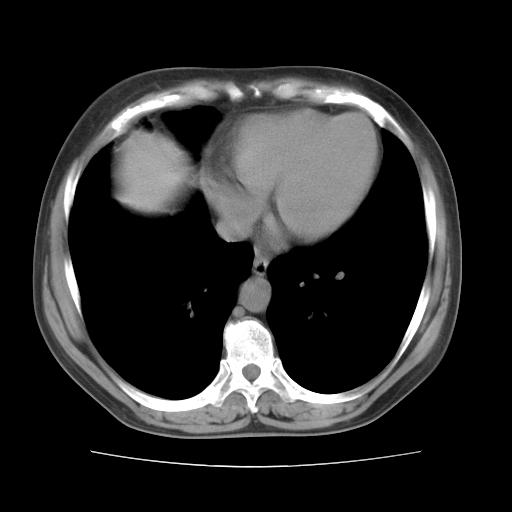

标题: CT10838:女性,56岁,是上腔静脉钙化还是淋巴结钙化?

女性,56岁临床诊断为胃贲门ca,术前检查发现,此钙化灶,对此科内稍有争论!请各位老师看看!是上腔的还是淋巴结的?有意义吗?

淋巴结钙化,上腔静脉在外侧可看到.

支持淋巴结钙化,气管前胸骨后也有.

考虑:上腔静脉后淋巴结钙化,没有什么意义。

左锁骨下静脉和头臂静脉会合后形成是上腔静脉,此钙化位于两血管回合的腔静脉后方、气管右前方,这个位置没有其他结构,应该是淋巴结钙化。一般多为淋巴结核后钙化,没有临床意义。